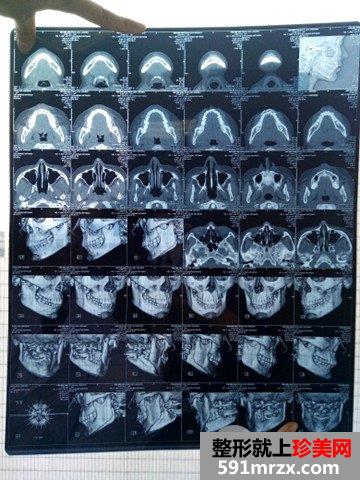

术前是肯定要拍CT的,明显得看出两边不一样吧

医生说会在最安全的范围类去掉突出的下颌角